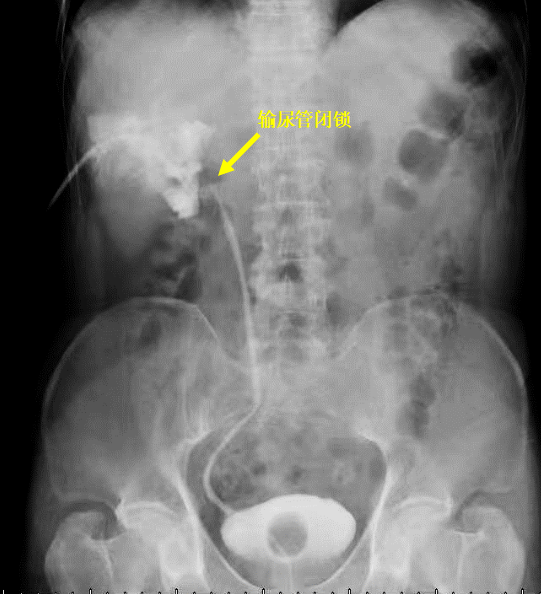

李先生常年受结石困扰,做过体外碎石。4月前,李先生又突发剧烈腰痛腰酸,去医院就诊时CT检查发现右肾积水、右输尿管结石、肾结石。于是,当地医院为李先生做了输尿管钬激光碎石手术,术中发现右侧输尿管狭窄。术后复查显示,肾积水并没有好转于是,李先生在当地医院进行了肾造瘘,造瘘后造影提示肾门部输尿管狭窄完全闭锁。

图片2.png